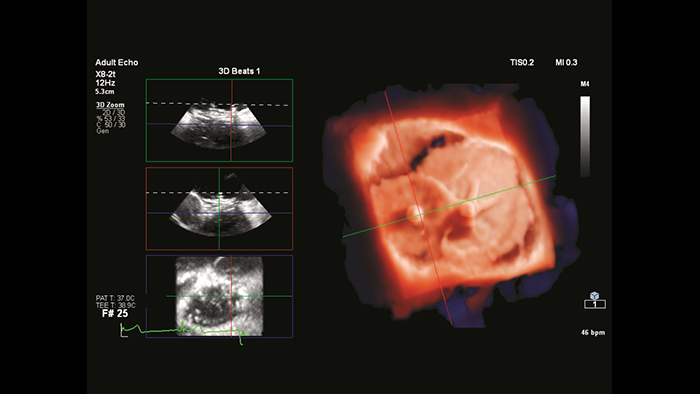

Información detallada con TrueVue color y GlassVue

Representación fotorrealista de TrueVue cardiaco con alineación de imagen de MultiVue

Segmentación del modelo cardiaco de EchoNavigator